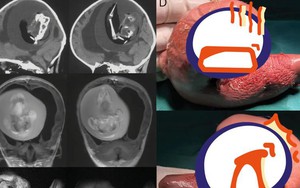

Mang thai đôi nhưng chỉ sinh một bé, 1 năm sau bố mẹ đưa con gái đi khám mới phát hiện sự thật đáng sợ nằm trong não

Kết quả chụp CT não đã khiến gia đình lẫn các bác sĩ bất ngờ vì là trường hợp siêu hiếm trên thế giới.